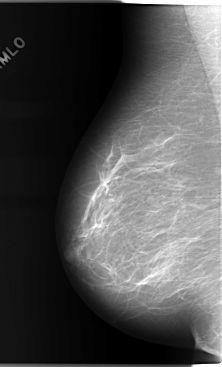

C_0103_1.LEFT_MLO

LEFT_MLO LINES 5864 PIXELS_PER_LINE 3528 BITS_PER_PIXEL 12 RESOLUTION 50 OVERLAY